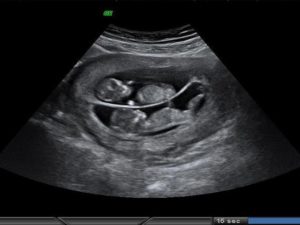

Следовательно, наличие двойняшек в утробе выявляется посредством ультразвука уже через месяц после зачатия, на снимке они выглядят как 2 образования темного цвета внутри полости матки (см. фото УЗИ-обследования двойни ниже).

• УЗИ-диагностика двойни через 11 недель показывает немного уменьшенные для своего срока развития размеры первого и второго плода – примерно 4,2-4,8 см.

• При обследовании на 12 неделе эмбрионы имеют длину по 6 см, а их вес составляет примерно 8 грамм.

• На 20 неделе малыши имеют вес 350 грамм. Можно заметить, что один ребенок крупнее второго. Это происходит из-за кровяного шунта, по которому происходит постоянный сброс крови одному из двух плодов.

• После 32-34 недель малыши набирают вес до 2 кг.

Увидеть двойню на УЗИ при беременности можно уже через месяц после зачатия. В этом случае специалист отметит на экране монитора два пятна черного цвета, которые хорошо просматриваются ультразвуком